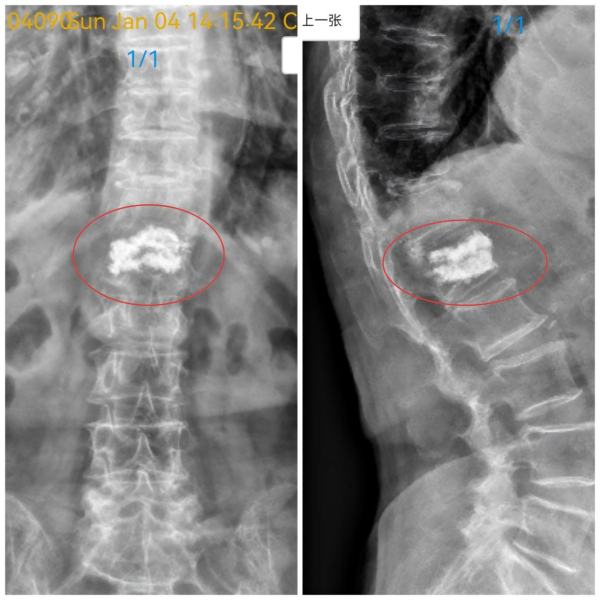

图2:术后腰椎X片检查显示椎体恢复,骨水泥分布良好